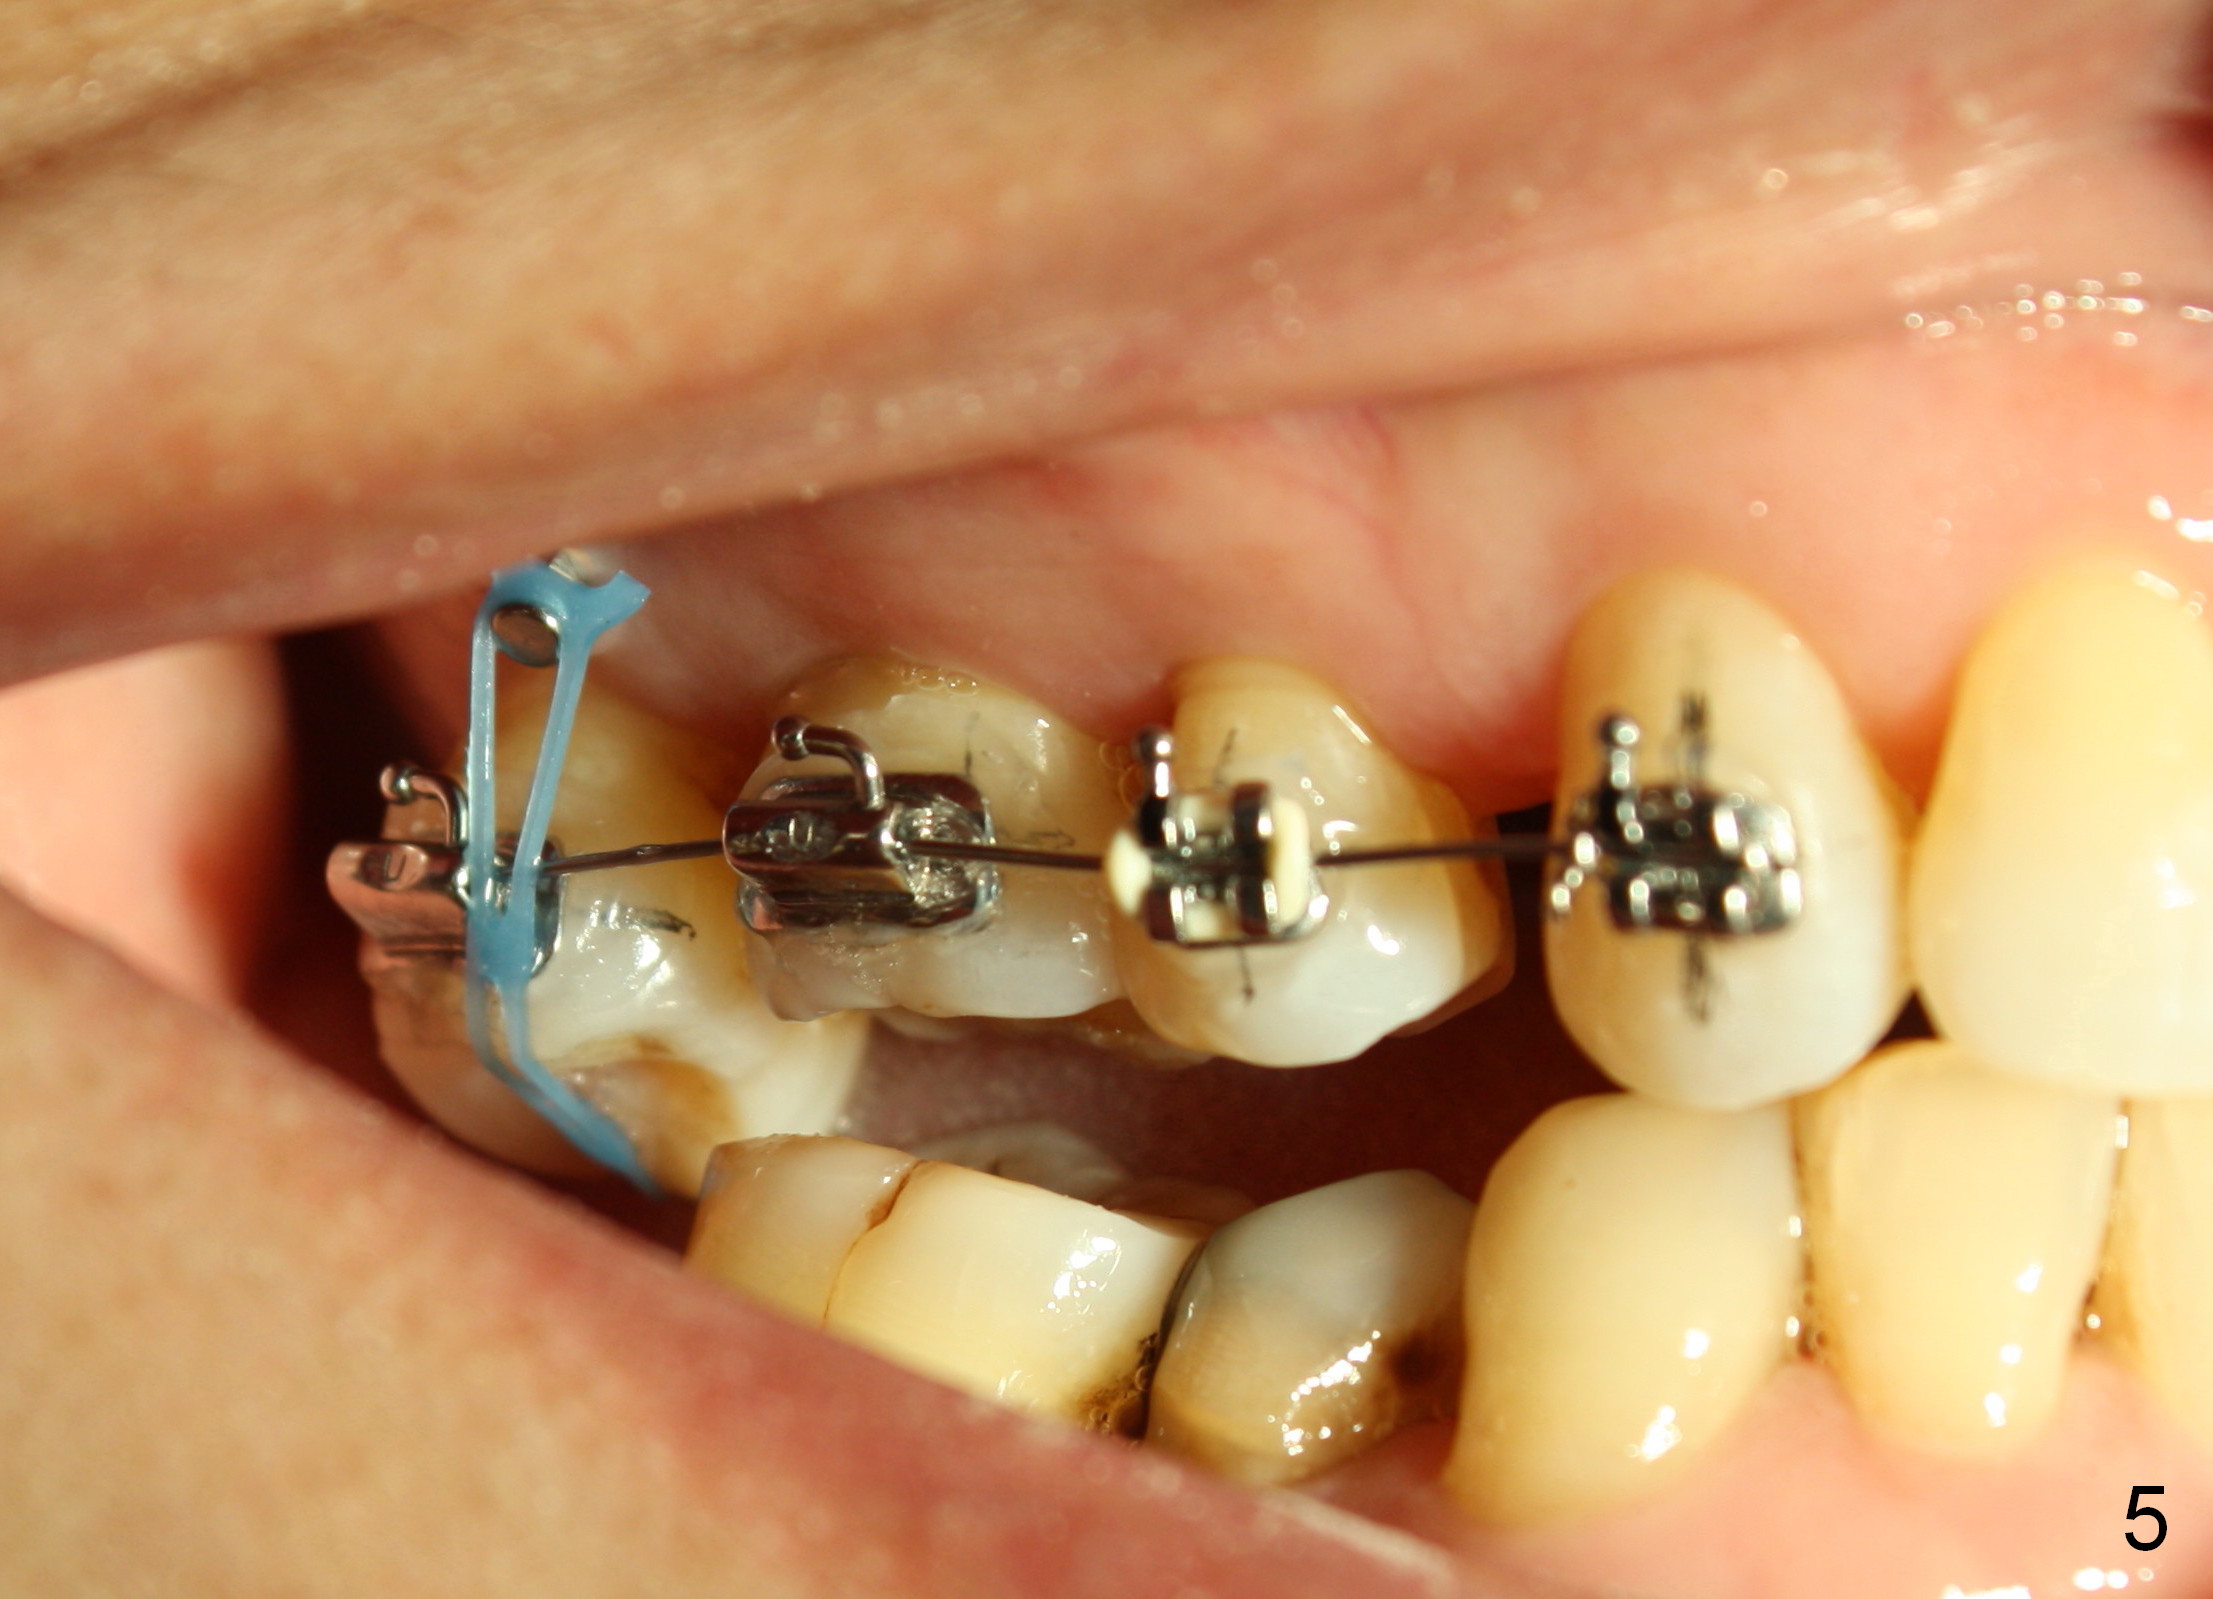

The wound of 2 stage implant surgery is found to be gapping 10 days postop with healing screw exposure 2 weeks postop. Exam at a month postop (Fig.1) shows that the mesiolingual cusp of the upper right 2nd molar is sharp (Fig.2 <) and inserted into the wound of the implant site (Fig.3). Two mini-implants are placed with immediate power chain retraction (Fig.4). The orthodontic intrusion is without effect; brackets are placed 4 months later (Fig.5). Two months later, the patient is diagnosed to have breast cancer. As a precaution for chemotherapy, the orthodontic device is removed. During chemotherapy, the patient returns once. The gingiva around the cover screw is mildly erythematous and edematous. After removing plaque from the cover screw with irrigation, the patient feels a little better. All of the orthodontic appliances are removed before she receives chemotherapy for breast cancer.